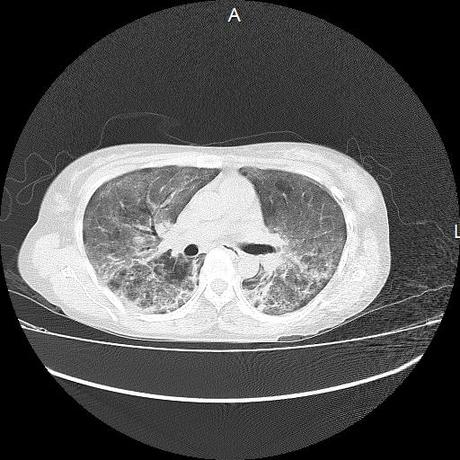

El parénquima pulmonar con areas parcheadas difusas en vidrio despulido combinadas con otras areas hipodensas de baja atenuación debidas a atrapamiento aéreo y engrosamiento intersticial y zonas de fibrosis de predominio en lóbulos medios e inferiores de ambos pulmones.

- LOS HALLAZGOS PUEDEN ESTAR EN RELACIÓN A NEUMOPATIA INTERSTICIAL PROBABLE ETIOLOGIA HIPERSENSITIVA VS AUTOINMUNE/BACTERIANA/FUNGICA.